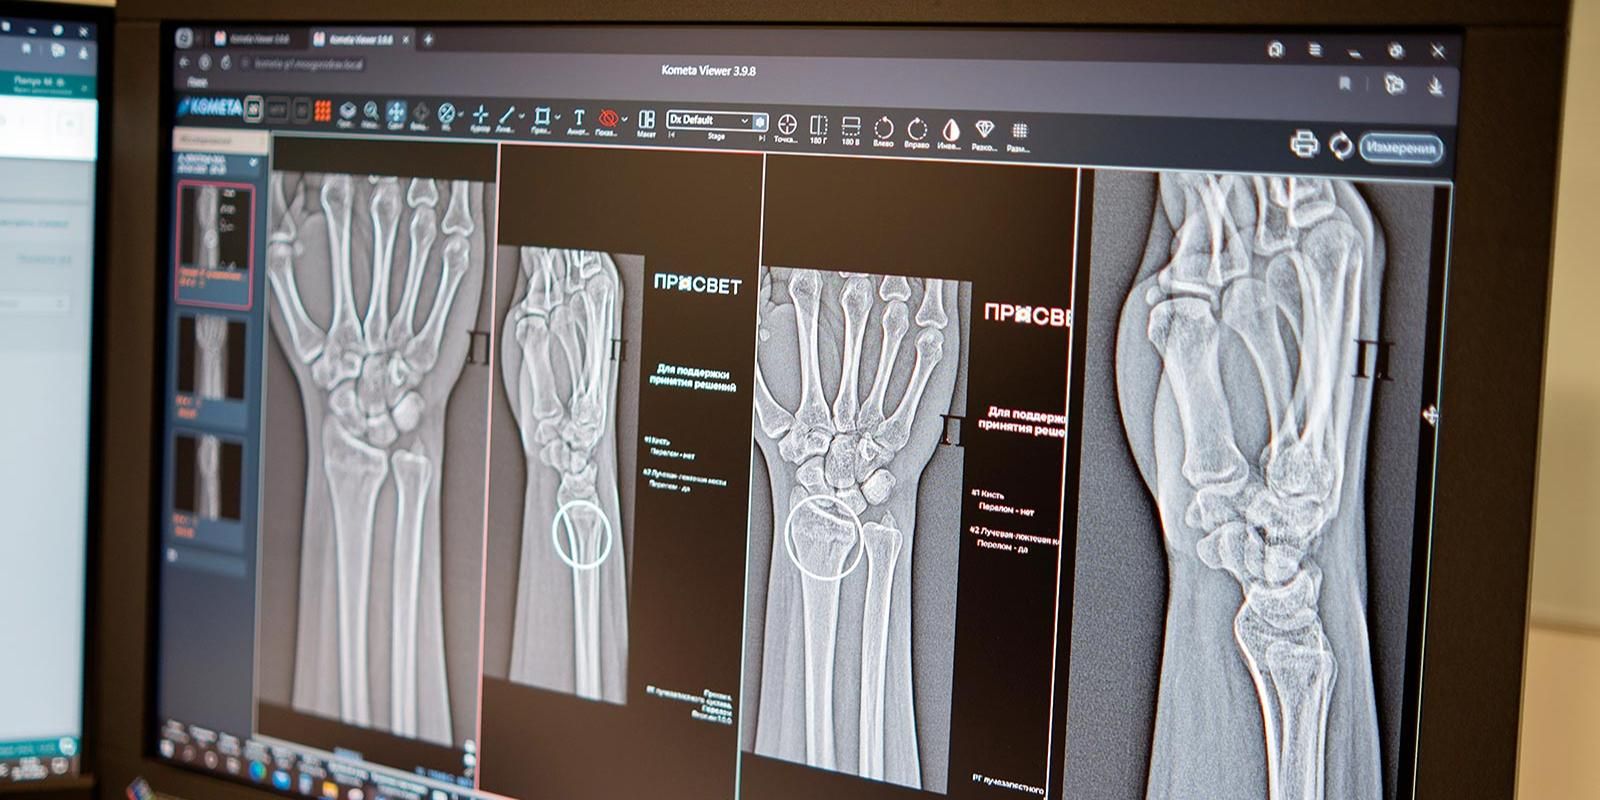

ИИ-травматология в Москве

Но не будем нагнетать и поговорим об успехах высоких технологий в служении человеку каждый день. Не без удивления узнал, что уже сейчас в Москве для определения по рентгеновскому снимку наличия или отсутствия перелома служат не только глаз и опыт врача, но и нейросеть. Всего ИИ-сервисов для врачей-рентгенологов уже более 60. Недавнее пополнение — система анализа снимков голеностопа и лучезапястного сустава. Их травмы — весьма частое явление, поскольку суставы очень нагруженные и очень ломкие, так что не редкость, когда на снимке сложная картина со старыми травмами или несколькими переломами. ИИ в данном случае врача не заменяет, а помогает ему: снимки анализируется быстрее, мелкие трещины находятся чаще и риск пропустить важное снижается. Нейросеть не выносит финальный вердикт, а лишь подсвечивает вычисленные алгоритмами зоны, в которых может быть проблема. В общем, как заявляется, врача-травматолога пока на свалку истории никто не выкидывает, но работать ему стало легче.